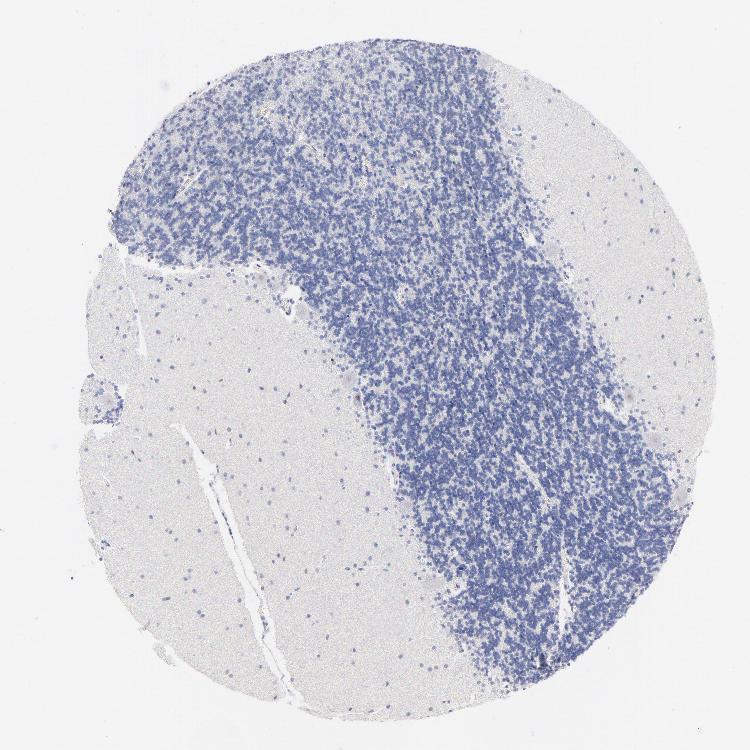

CEREBELLUM - Antibody stainingi

Antibody staining in the annotated cell types in the current human tissue is reported as not detected, low, medium, or high, based on conventional immunohistochemistry profiling in selected tissues. This score is based on the combination of the staining intensity and fraction of stained cells.

Each image is clickable and will lead to virtual microscopy that enables deeper exploration of all samples and also displays staining intensity scores, fraction scores and subcellular localization as well as patient and tissue information for each sample.

Antibody HPA003134Antibody CAB002625

Purkinje cells MediumNot detected

Cells in granular layer Not detectedNot detected

Cells in molecular layer Not detectedLow